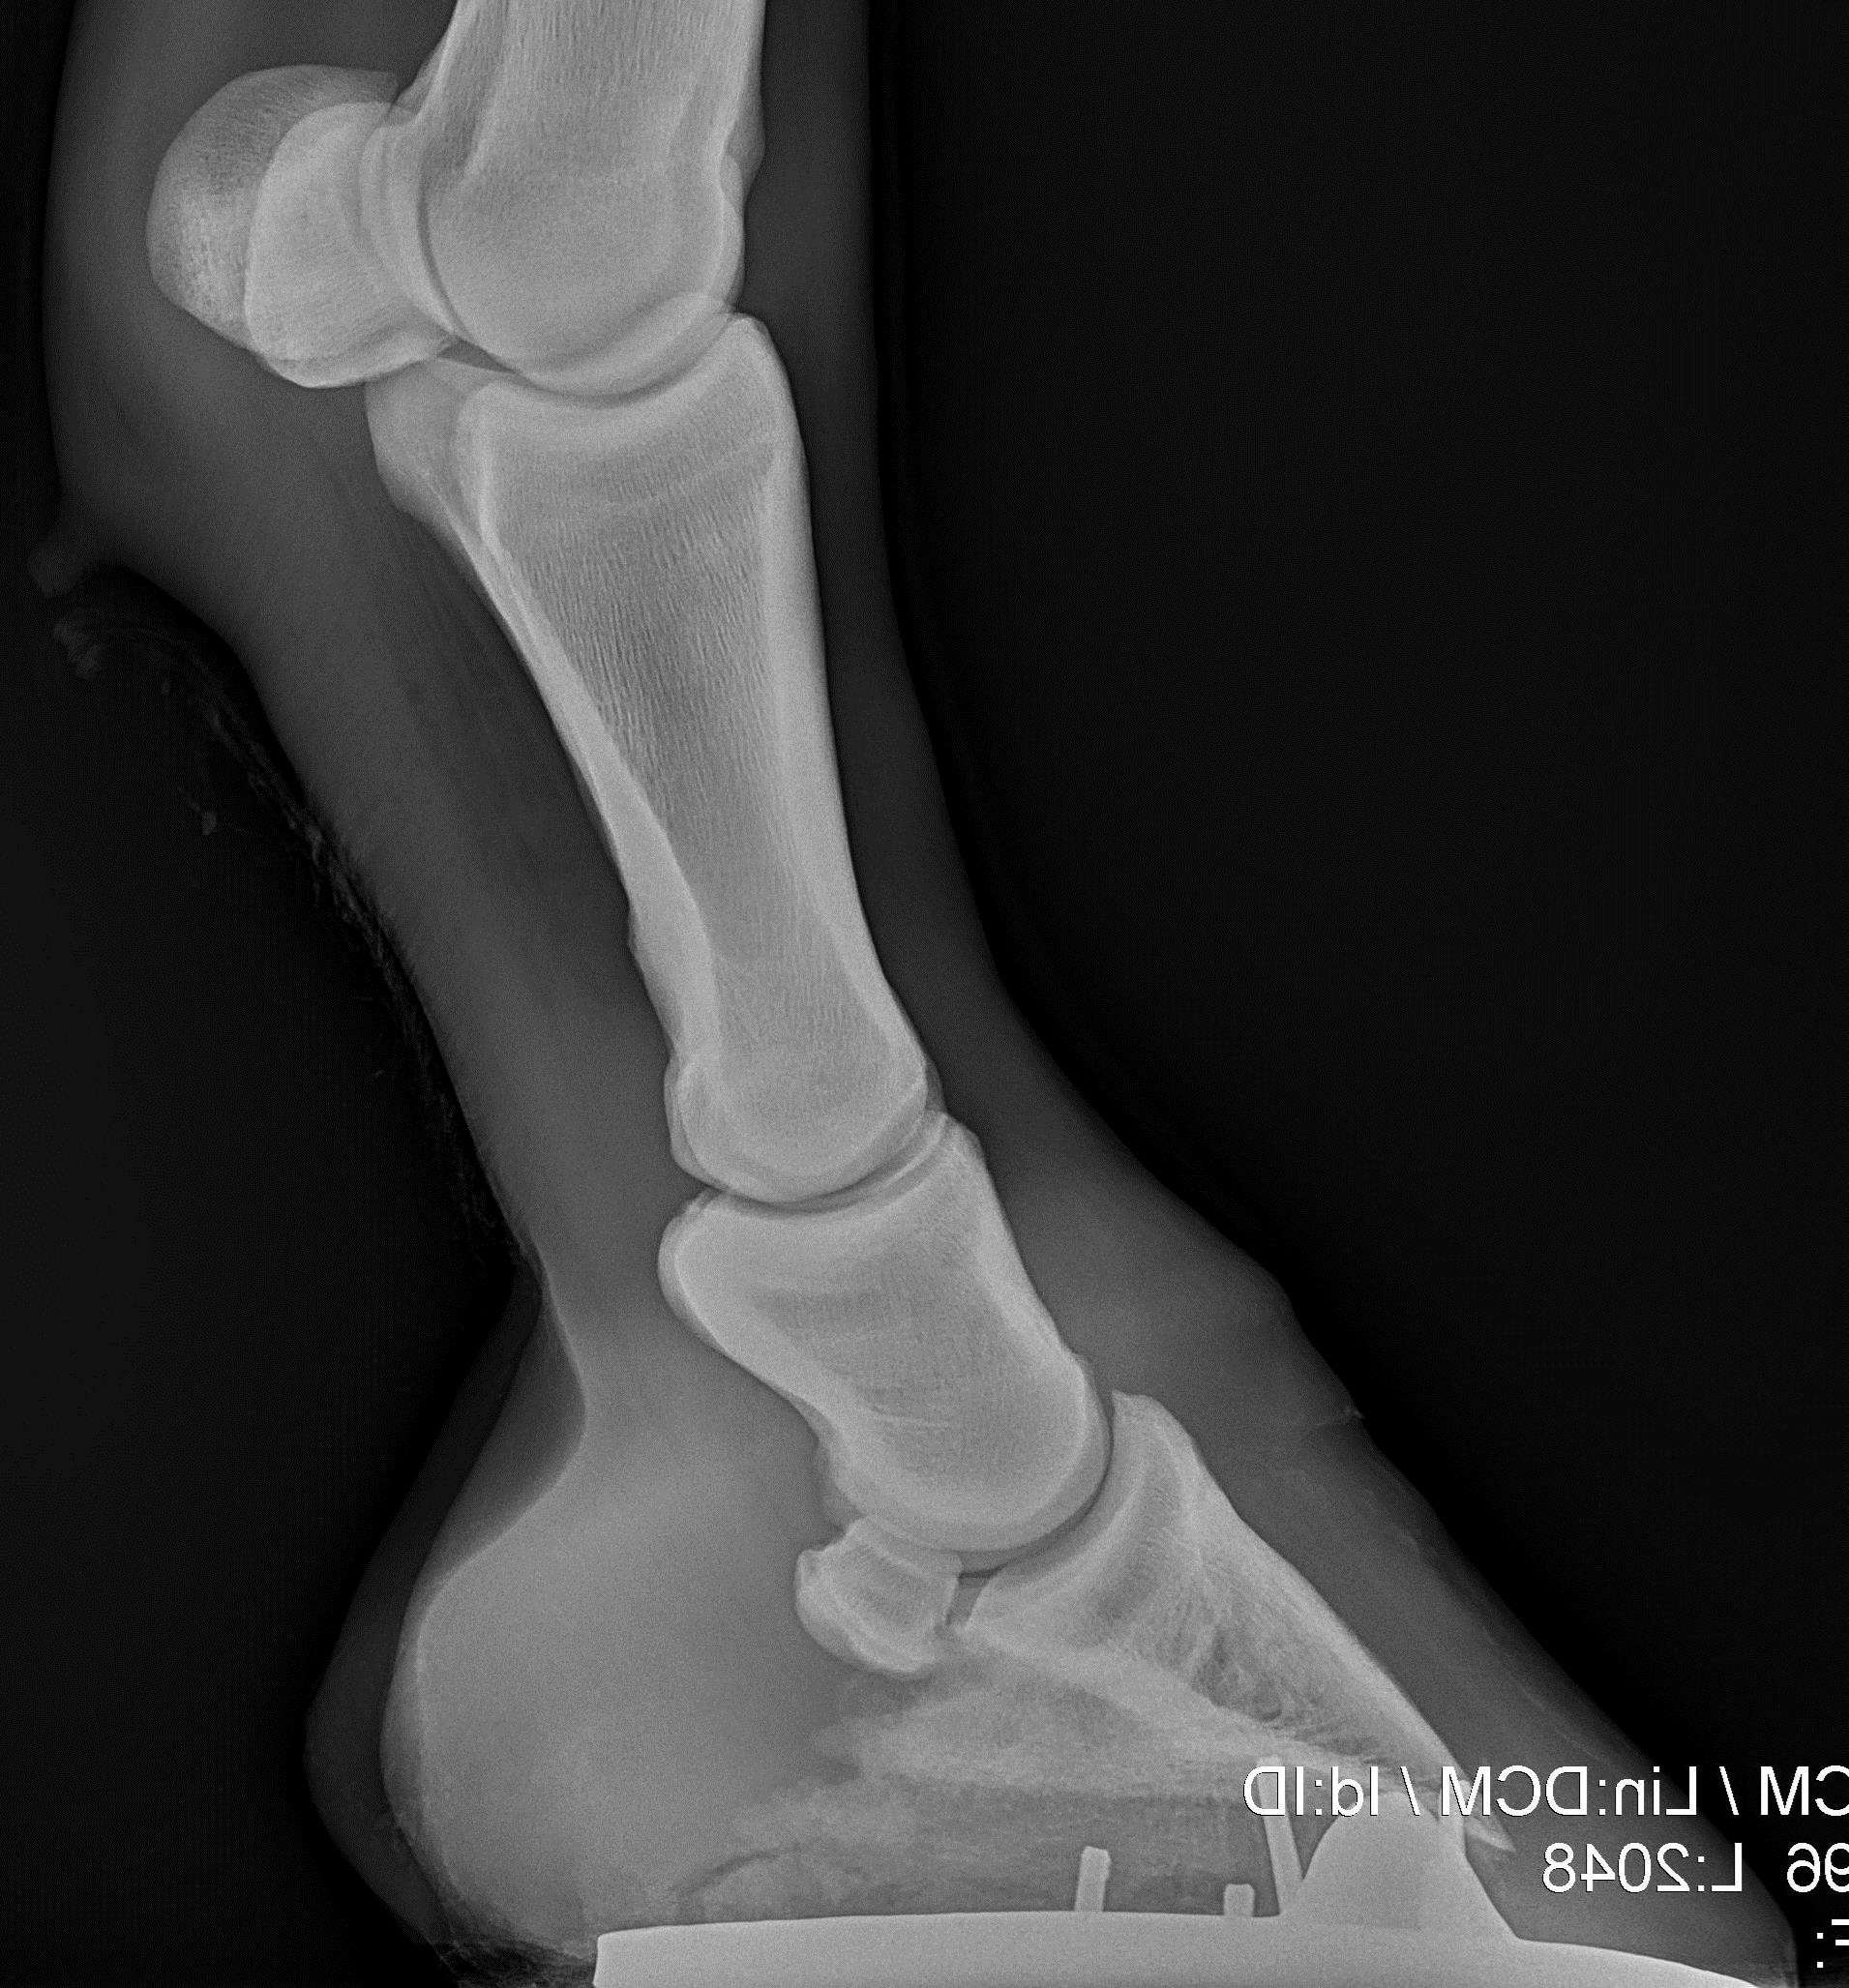

Inderst er hestens knogler. Den nederste knogle på billedet er hovbenet og det ligger inderst i hesten hov.​ I knoglen er der blodkar og nerver.

Røntgenbillede af hesten tå. Nederst ses hovbenet.​​